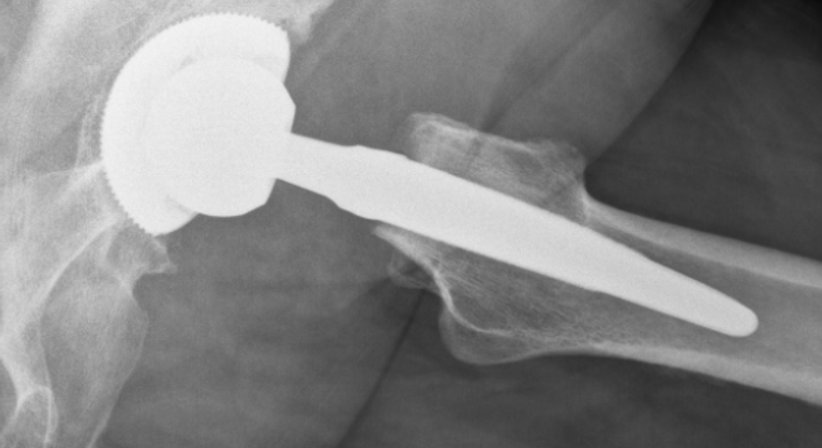

Wahl der Hüftprothese und des Operationzugangs

(minimal-invasive Hüftoperation nach der AMIS © - Methode)

Es stehen unterschiedliche Prothesen und Operationstechniken zur Verfügung, um das körpereigene Gelenk zu ersetzen. Der Eingriff kann minimal-invasiv oder offen erfolgen. Die minimal-invasive Methode bietet Patienten einige Vorteile, allen voran, dass die Muskulatur seitlich der Hüfte bei der Operation nicht durchtrennt wird. Dadurch werden Vernarbungen und Heilungsschmerzen an diesen für die Fortbewegung wichtigen Muskeln vermieden, was im Regelfall eine kürzere Rehabilitationszeit bedeutet. Patienten sind nach der Operation schneller wieder selbstständig mobil und können alltäglichen und sportlichen Aktivitäten wieder früher nachgehen. Welche Prothese und Operationstechnik im Einzelfall am besten geeignet sind hängt von der Ausgangssituation des Patienten und individuellen Faktoren ab. Sind die Voraussetzungen gegeben, dann führe ich Hüftimplantationen bei Möglichkeit minimal-invasiv (AMIS © - Methode) durch.

Der genaue Ablauf des Eingriffs und alle wichtigen Punkte (richtiger Zeitpunkt für die Operation, Wahl der Prothese, Verankerungsart, um die Prothese mit den Knochen der Hüfte zu verbinden etc.) werden nach Vorliegen einer exakten Diagnose eingehend besprochen und an die spezifischen Bedürfnisse und Anforderungen des Patienten angepasst.